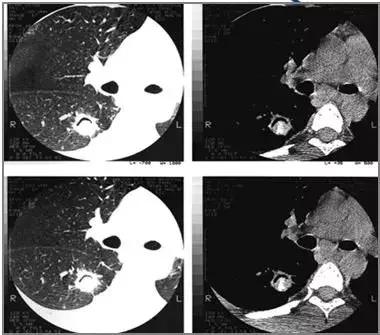

晕轮征(halo sign):是指结节周围环绕的类环形的磨玻璃样密度影。通常代表肺出血与水肿。一般是侵袭性真菌病的早期征象;也可见于炎症、肿瘤与结核病等疾病中。

霉菌球周围晕征

肺泡癌周围晕征

侵袭性肺曲霉菌病